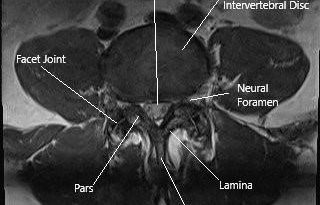

Uncovering Dual Origins of Lower Limb Claudication in a Rare Lumbar Facet Joint Case

Unraveling the Twists and Turns of Lower Limb Claudication Lower limb claudication is a condition that many in the medical community have encountered, yet its diagnosis and treatment can be riddled with tension and confusing bits. As an editor who explores both modern medicine and alternative approaches, I have been intrigued by recent cases that […] More